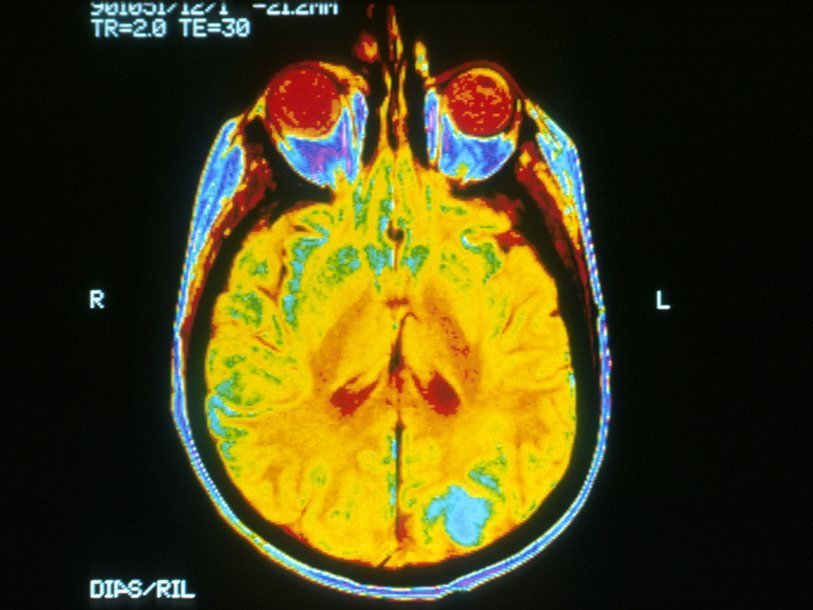

Психологи и программисты из ведущих университетов США и Великобритании объединились для совместного проекта по анализу политических взглядов по результатам функциональной магнитно-резонансной томографии. 83 здоровых добровольца должны были описать свои политические убеждения, согласившись с рядом утверждений или отвергнув их. По результатам опроса участников разделили на три практически равные группы: консерваторы, либералы и люди умеренных политических взглядов. Затем каждого добровольца помещали в МРТ-сканер, где под видом изучения зрительного восприятия показывали в случайном порядке 80 изображений. Их состав был таким: 20 приятных (котенок, кролик, дельфин), 20 нейтральных (ложка, фонарик, пожарный кран), 20 вызывающих отвращение (тараканы в еде, рвота, последствия ожогов) и 20 устрашающих (взрыв, сцены ограбления, падения самолётов и т.д.).

ФМРТ позволяла отследить, какие области мозга активируются у испытуемых во время просмотра того или иного изображения, и с какой силой. Данные, полученные этим методом, сопоставили с результатами опроса, посвященного политическим взглядам. Оказалось, что по активации тех или иных участков мозга во время просмотра отвратительных картинок можно было с высокой точностью определить, к либералам или консерваторам относится испытуемый. При этом эмоциональные оценки, которые давали изображениям сами участники исследования, могли не совпадать с результатами фМРТ и не давали такого четкого представления об убеждениях людей, как данные томографического исследования. Ответы мозга на приятные, пугающие и тем более нейтральные изображения, казалось, никак не были связаны с политическими взглядами участников.